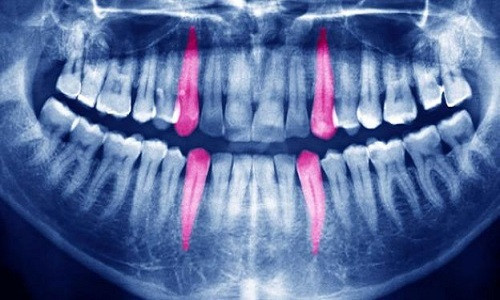

| Nhiều giả thuyết được đưa ra về hiện tượng răng phát nổ trong miệng người bệnh. Ảnh: Alamy. |

Trong một bài viết vào năm 1860, Atkinson đưa ra hai hướng lý giải cho hiện tượng kỳ lạ này. Theo giả thuyết thứ nhất, chất calo được hình thành trong răng, làm tăng áp lực lên tủy răng. Giả thuyết này bị bác bỏ ngay lập tức vì nó dựa trên một lý thuyết khoa học lỗi thời cho rằng calo là chất chống thấm có khả năng làm tăng áp lực. Tuy nhiên, khoa học đã chứng minh chất này không tồn tại.

Giả thuyết thứ hai là sâu răng làm tăng lượng khí tích tụ trong răng khiến răng phát nổ. "Chúng ta không rõ khí tích tụ trong răng có đủ làm răng phát nổ không vì răng có cấu trúc rất chắc chắn. Các nha sĩ thế kỷ 19 không hiểu về sâu răng. Họ cho rằng sâu răng đến từ bên trong nhưng thực chất đó là do chế độ ăn uống và lượng vi khuẩn tích tụ trên bề mặt răng gây ra", giáo sư Devlin phản bác.